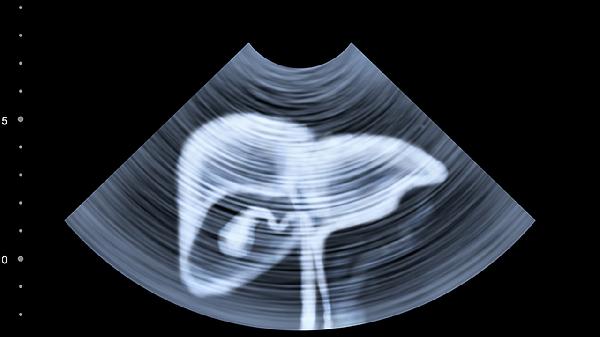

1、B超检查的优势在于无创、便捷,能够实时观察肝脏的形态和血流情况。通过B超,医生可以发现肝脏肿大、脂肪肝、肝硬化、肝囊肿、肝血管瘤等病变。对于肝脏肿瘤,B超也能初步判断其位置、大小和性质。然而,B超对早期肝病或轻微肝损伤的敏感性较低,可能无法发现微小病变。

5、综合多种检查方法,能够提高肝病诊断的准确性。B超作为初步筛查手段,结合血液检查、CT或MRI,能够全面评估肝脏健康状况。对于复杂或疑难病例,肝活检能够提供确诊依据。早期发现和诊断肝病,有助于及时治疗,改善预后。

肝病通过B超检查可以初步发现异常,但确诊需结合血液检查、CT、MRI等多种手段。早期诊断和综合治疗是改善肝病预后的关键,定期体检和健康生活方式有助于预防肝病。